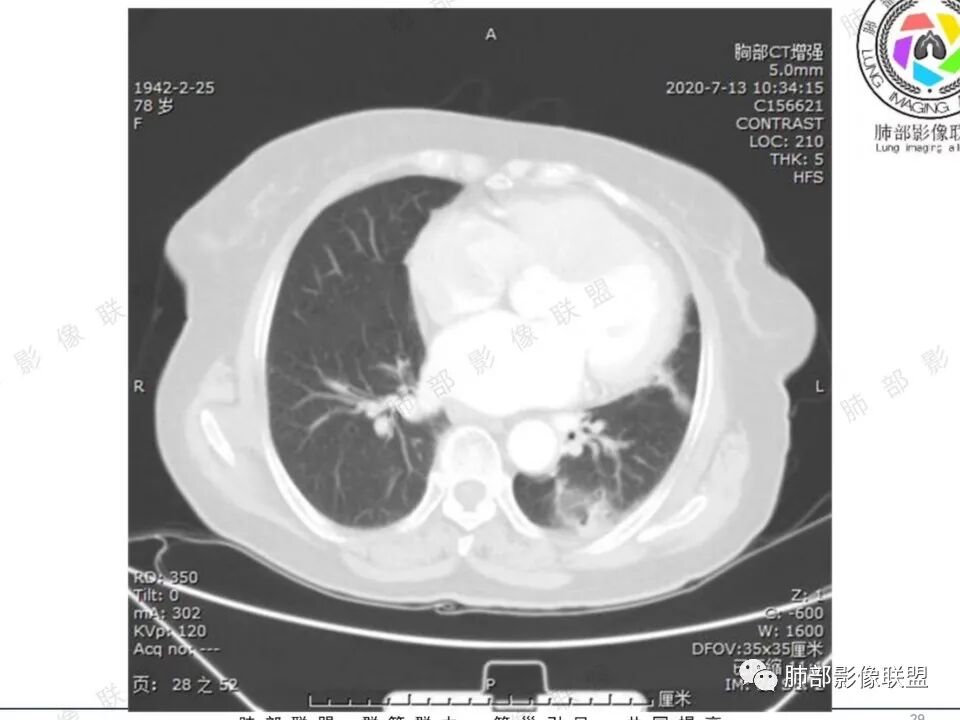

穿越七海的风: 右肺下叶不规则结节伴空洞,似鬼脸,壁厚度不均,壁内结节,首先考虑恶性,既往甲状腺癌病史,不除外转移。

蔡笑燕: 右肺不规则实性囊腔结节,囊腔内有血管走形和分隔,有分叶,细短毛刺,周围有清晰磨玻璃,胸膜牵拉,考虑IAC。

看图说话: 不规则结节,假大空,壁结节,边缘收缩,胸膜牵拉,周围有分叶,毛刺,伴有清晰磨玻璃影,周围有小结节,考虑肺腺癌,鉴别:1:结核,2,隐球菌。

哦落花时节 (刘朋): 中青年男性,右肺下叶不规则结节,内见多发囊腔,囊腔内壁不光滑,邻近叶间裂明显局部凹陷,有胸膜牵拉,血管聚集,考虑囊腔性腺癌,鉴别转移。

清茶: 青年男性,右肺下叶高密度结节影,有毛刺、分叶,内见空洞,边界尚清,考虑恶性,腺癌可能。

王秀仙: 右下肺 囊腔性结节,囊壁不均匀增厚,壁结节,毛刺分叶,胸膜凹陷,周边有边界清楚磨玻璃影,考虑囊腔型肺癌,腺癌。

心灵鸡汤: 青年男性,有甲状腺癌穿刺活检病史, 右肺下叶不规则囊腔,内壁不光整,似见壁结节,偏远侧见实性结节,病灶边缘可见分叶,毛刺,邻近血管支气管走行不自然,邻近斜裂牵拉,考虑二元,恶性结节,腺癌可能性大,转移、结核待排。